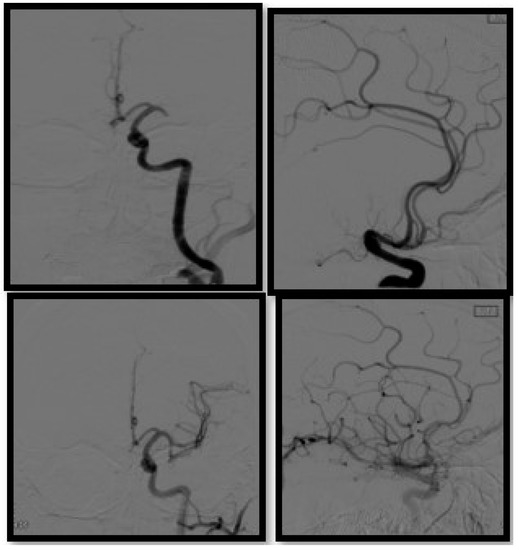

- Artico, M.; Spoletini, M.; Fumagalli, L.; Biagioni, F.; Ryskalin, L.; Fornai, F.; Salvati, M.; Frati, A.; Pastore, F.S.; Taurone, S. Egas Moniz: 90 Years (1927–2017) from Cerebral Angiography. Front. Neuroanat. 2017, 11, 81. [Google Scholar] [CrossRef] [Green Version]